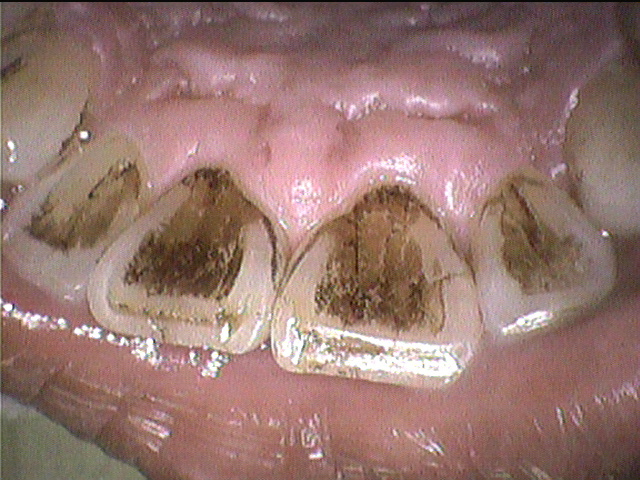

クリーニング前

下の前歯と上の前歯の裏側の写真です。

ステインがとてもつきやすく、3ヵ月毎にクリーニングにいらしています。

ステインに加えて歯石もついていましたが、しっかり除去し綺麗になりました。

この患者さんはコーヒーと赤ワインをよく飲まれているそうなのですが、

この2つはステインが特につきやすい飲み物です。